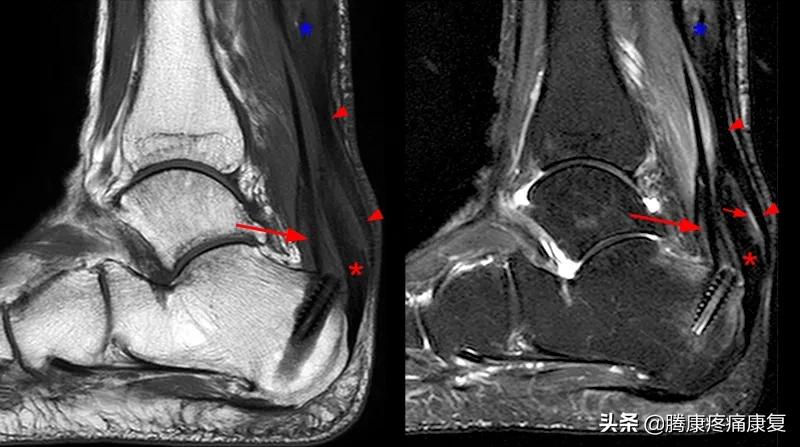

跟腱炎的诊断与鉴别

跟腱处出现疼痛、肿胀等症状,在脚跟受力或活动后加剧。查体时检查到患处跟腱肿胀、发红、僵化、增厚等症状,按压时是否疼痛。还要注意脚跟处骨和关节的活动性。还可以通过B超、X线、MRI辅助检查来与跟骨骨折、踝关节骨折脱位、踝关节炎相鉴别。